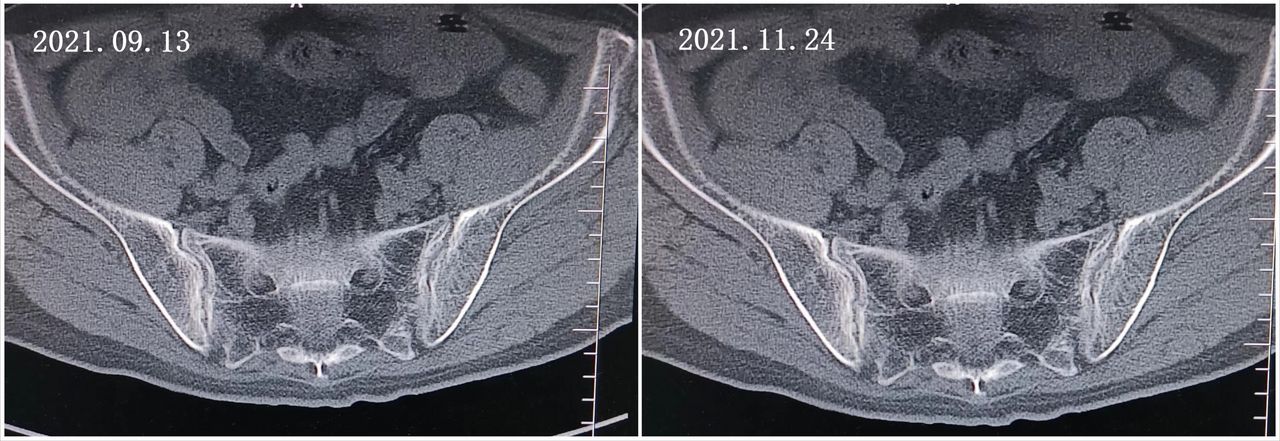

CT示骶髂关节间隙狭窄,彩超示双膝关节积液。

(髋关节CT)